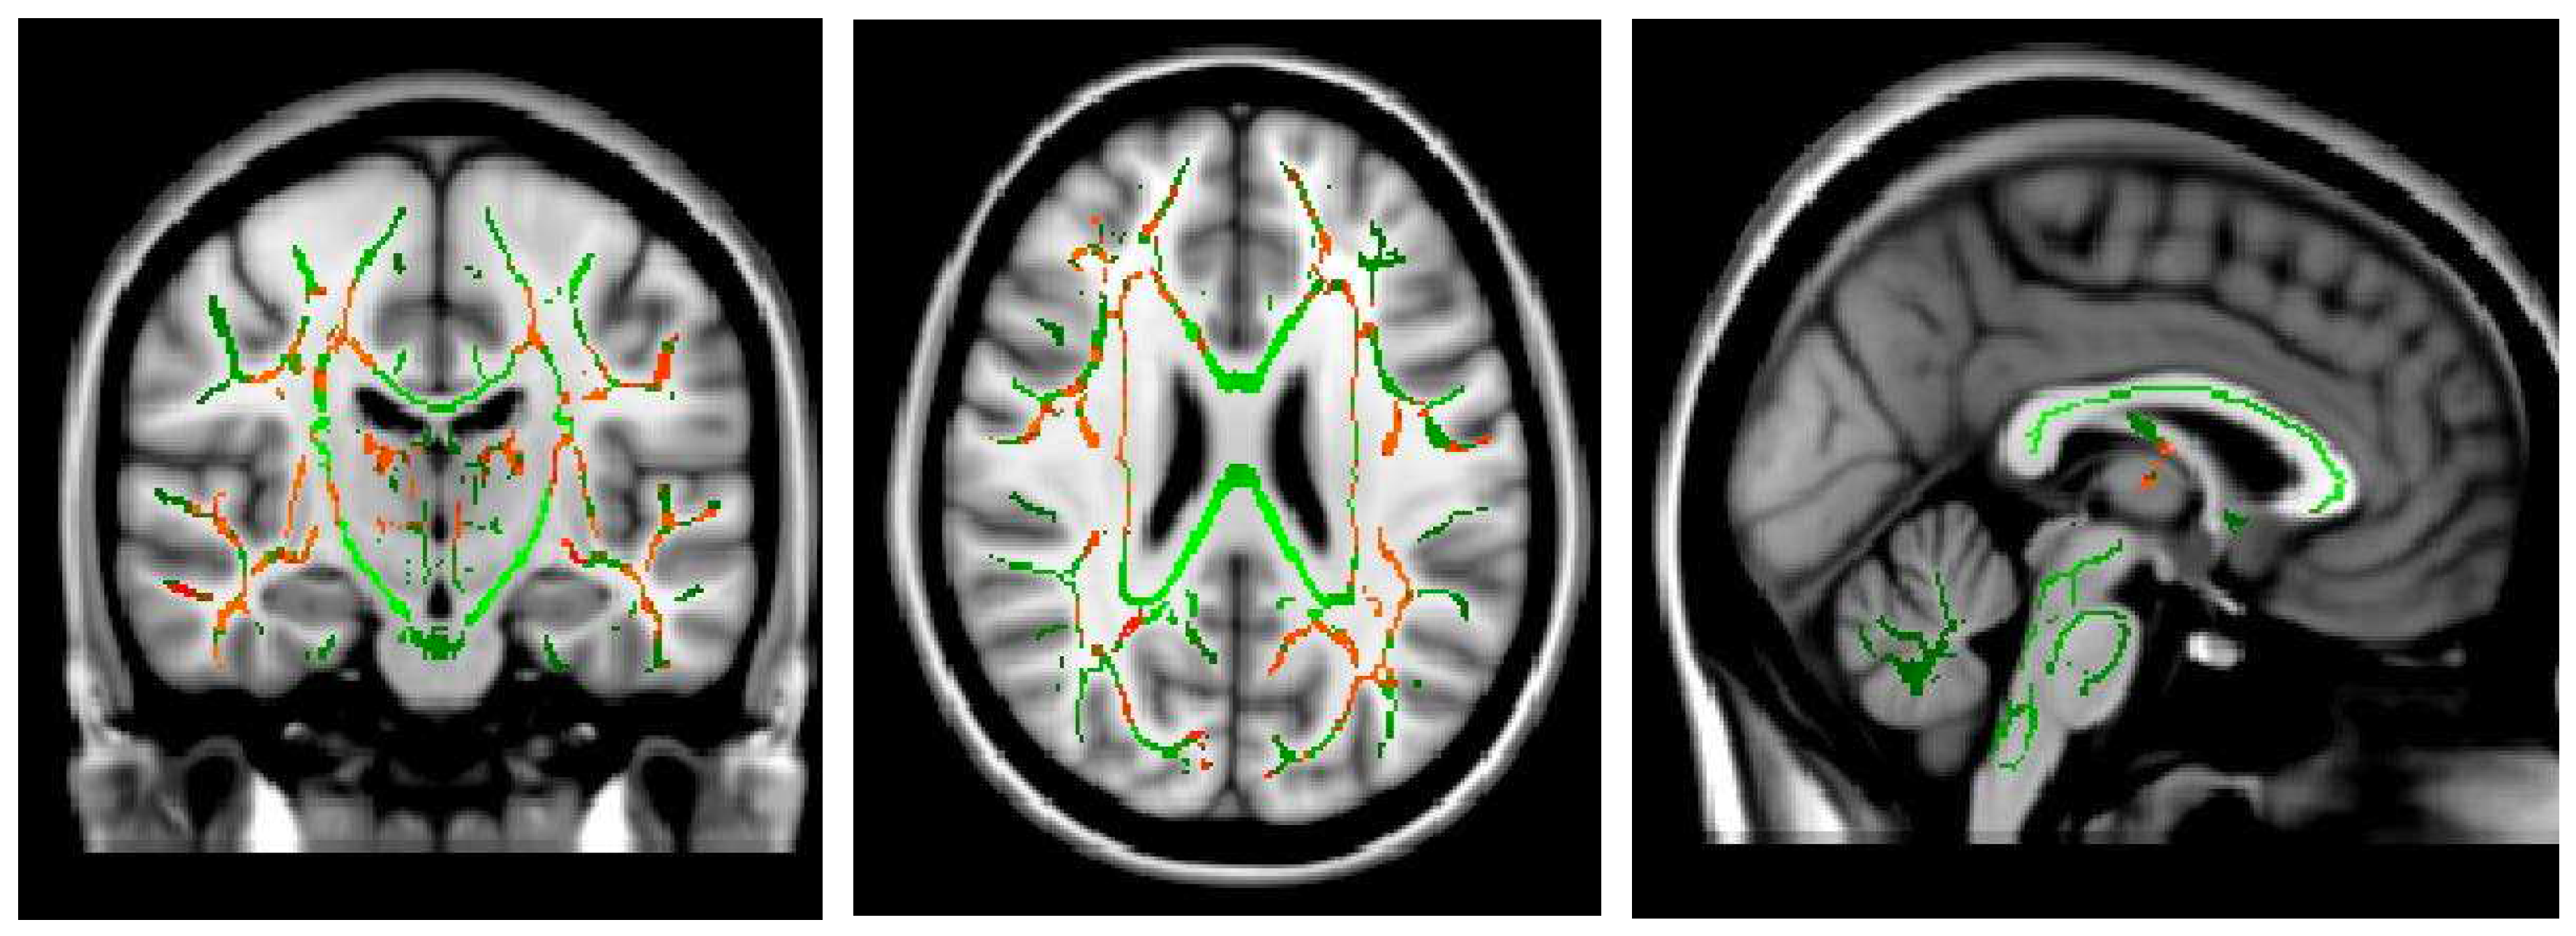

- Shibata Y, Ishiyama S, Matsushita A: White matter diffusion abnormalities in migraine and medication overuse headache: A 1.5-Tesla tract-based spatial statistics study. Clinical Neurology and Neurosurgery 2018, 174, 167–173. [CrossRef]

- Smith SM: Tract-based spatial statistics. NeuroImage 2006, 31, 1487–1505.